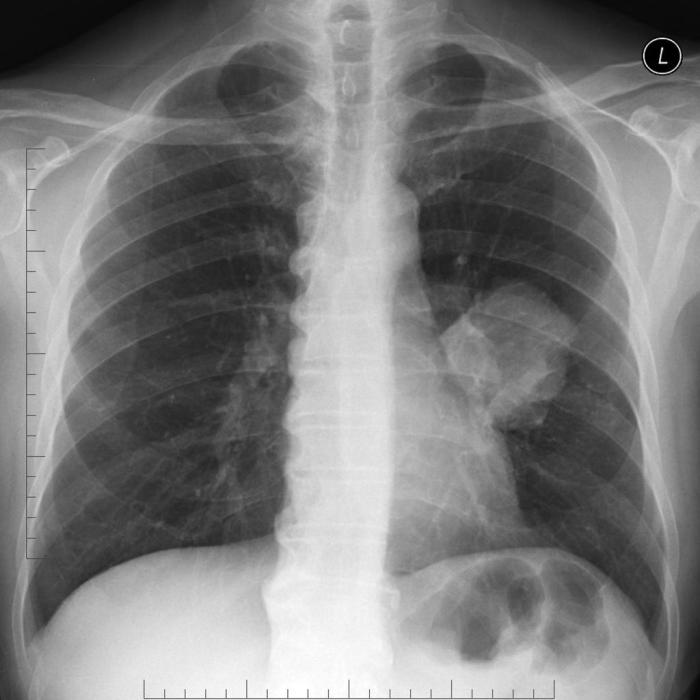

Our patient has known stage 4 metastatic lung cancer. His wife called EMS today because he has become progressively confused, nauseous, constipated, and fatigued over the past week.

This 63-year old man with known lung cancer presents with confusion, nausea and fatigue. Acute hypercalcemia of malignancy is diagnosed and needs to be treated. At the same time, a discussion with the wife (and substitute decision maker) will confirm that the patient wants active treatment but does not really have a clear idea of his prognosis. When pressed, the provider should deliver the bad news of the hypercalcemia compassionately and explain the context of an incomplete work-up in the ED. He should be referred for an in patient work-up with appropriate specialist consultation.